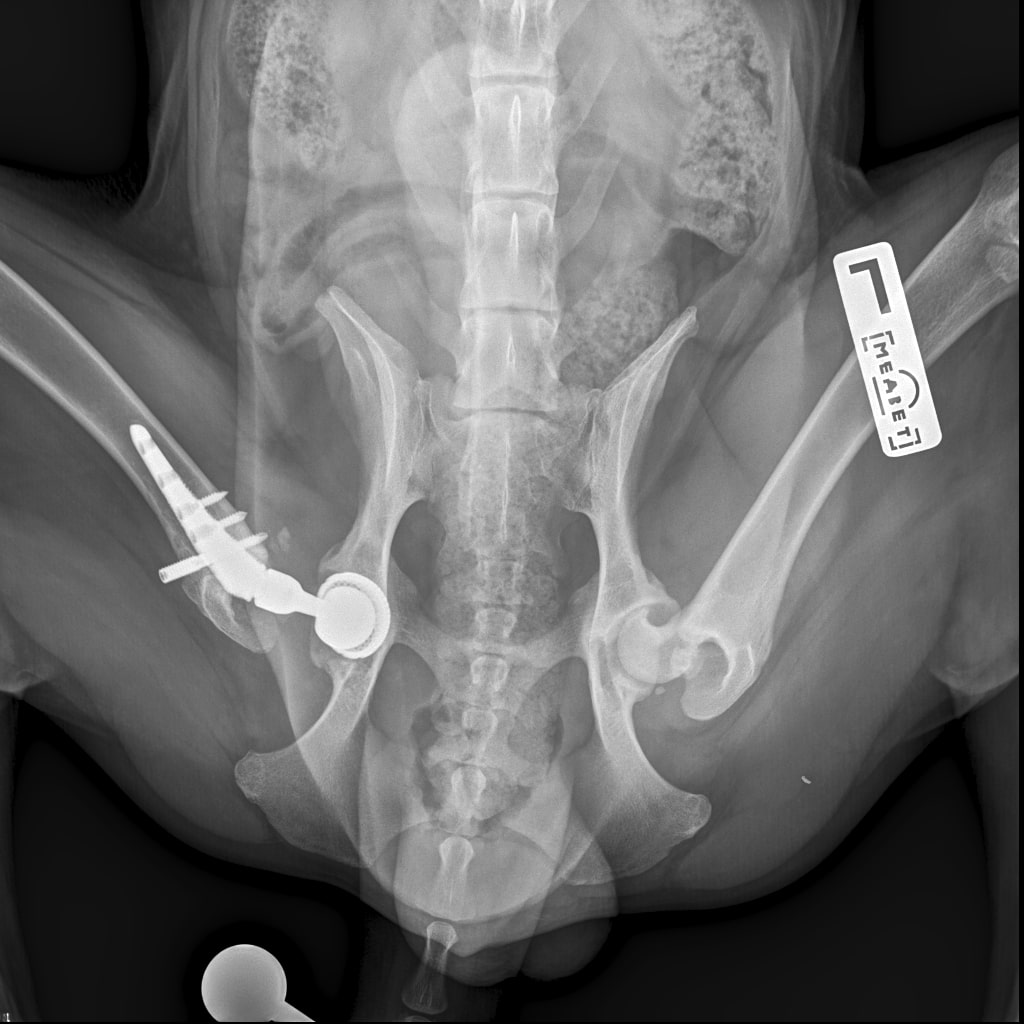

F37B4905-A77F-43B7-A3A7-4AAD9E739F82.jpeg

E6A744CC-768F-480D-8917-7FDAD53F05BD.jpeg

DA1A1524-BA63-434B-95BE-C121F7D5334F.jpeg

4D4A6426-4FE5-4417-ACCB-6DE53B57B90E.jpeg

E358D56E-67BF-4D4C-B3F0-BF8F4089D7A2.jpeg

767DD36C-E2E2-41FB-9CCF-6940421D2BB2.jpeg

701487DA-D6D9-4CE0-B18B-EEB120E78EF2.jpeg

Мы ничего не оплачивали. Все включено.

За время противовоспалительной терапии снизилось воспаление и в левом тазобедренном суставе, но увы, форма головки бедренной кости и состояние шейки бедра , лучше не стали:(((

Операция однозначно нужна.

Снимки столь качественные, что их можно в учебник